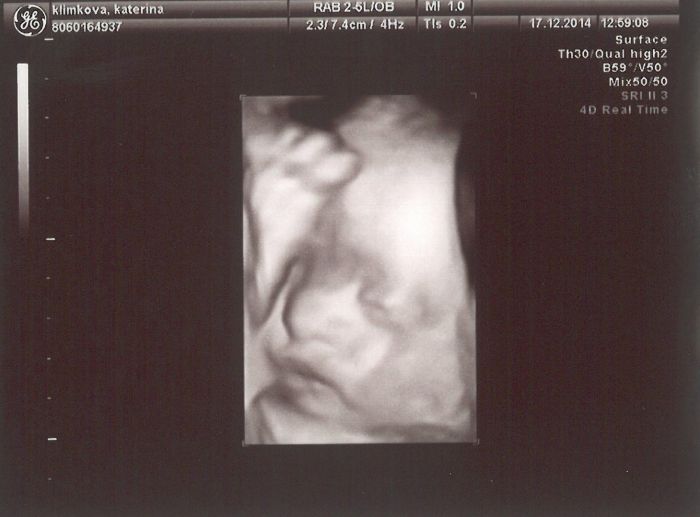

Díky holky, jste hodné. Já jsem na to také koukala, že to je normální váha, tak nevím co doktorka blbla :) Jinak s tím pediatrem jsem s ejí ptala, jestli ho už mám shánět a ona že už jsem ho dávno měla mít nakontaktovaného. Tak v lednu zkusím někoho najít... Jinak vám sem hodím fotky z 3D ultrazvuku. Mála Amélka se i smála a prý má nos po tátovi...to říkala ta doktorka. Ale přítel ho má nadvakrát zlomený, tak jsem zvědavá, co se nám narodí :)))) Ale zatím vypadá celkem lidsky :))))